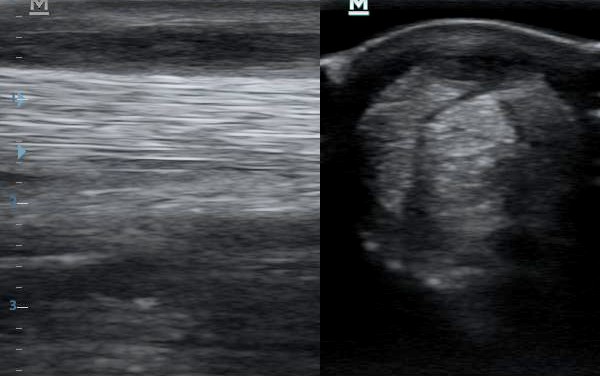

Ezt látjuk a vizsgálat során. Bal oldalon hosszmetszetben, jobb oldalon keresztmetszetben.

Ugyanaz a felvétel, az elváltozások bejelölve. Bal oldalon a piros nyilak jelzik a sérült ín sávját. Az egyenes, erős, fehér csíkok helyén fekete mező. A jobb oldalon körberajzolva az ín teljes keresztmetszete, azon belül a sérült rész. Az erős, fehér pettyezettség helyett fekete mező.